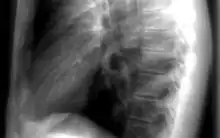

Les informations provenant des différentes structures traversées par le faisceau de rayonnements sont projetées sur un même plan pour former l'image. Par conséquent, il est souvent nécessaire de réaliser deux projections, à différentes incidences, pour pouvoir localiser une structure dans les trois dimensions de l'espace. Par exemple, en médecine, il s'agit fréquemment d'incidences de face et de profil. La loi d'atténuation des photons explique l'atténuation différentielle du faisceau à travers différentes structures, ce qui est à l'origine du contraste radiographique.

L'objet à radiographier, placé entre les positions et , à distance de la source pour que l'on puisse considérer qu'il est soumis à faisceau homogène de photons X ou gamma. Au fur et à mesure que le faisceau de photons traverse l'objet, il est atténué en fonction de l'épaisseur traversée et du coefficient d'atténuation . Ce coefficient d'atténuation dépend de l'énergie du photon et du numéro atomique Z de la structure rencontrée à la profondeur . L'organisme humain possède des tissus comme les os, très opaques aux photons, possédant donc un coefficient d'atténuation très élevé. Cela vient du fait que le tissu osseux est composé d'éléments de numéro atomique élevé comme le calcium. Le corps est aussi composé de tissus mous, peu opaques aux rayons X. Parmi eux, on différencie les organes de densité hydrique car composés essentiellement d'eau (muscles, foie) des densités graisseuses dont le coefficient d'atténuation est légèrement plus faible. Enfin, le poumon étant essentiellement composé d'air, il est qualifié d'organe de densité aérique. En effet le tissu pulmonaire, comme l'air, laisse passer la quasi-totalité des rayonnements. À la sortie du patient, le faisceau de photons n'est plus homogène mais est caractéristique des tissus traversés, on parle d'image radiante . Ces photons interagissent avec le détecteur, y déposant une énergie représentative des tissus traversés. Selon le mode de fonctionnement du détecteur, cette énergie sera utilisée pour produire l'image. La forte différence de coefficient d'atténuation entre les os et les autres tissus, crée un fort contraste de l'image, ce qui fait des rayons X un excellent outil d'imagerie osseuse. Pour obtenir une image d'organes n'ayant pas une densité spécifique, il est possible d'apporter in situ un produit de contraste de forte densité. C'est le cas pour l'imagerie des vaisseaux (injection intraveineuse d'iode), pour l'imagerie du système digestif (ingestion ou injection de baryte, à base de baryum), pour l'imagerie des articulations, ou arthroscopie (injection intra-articulaire d'iode) ou encore par exemple pour l'imagerie du système de reproduction de la femme, ou hystéroscopie (injection d'iode).